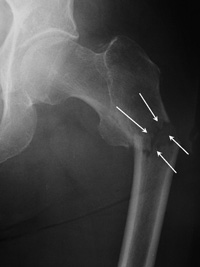

Subtrochanteric Fracture. This occurs even further down the bone and may be broken into several pieces.

Repair of subtrochanteric fracture with a long intramedullary nail.

Interlocking screws at the end of the nail make the fixation more secure.